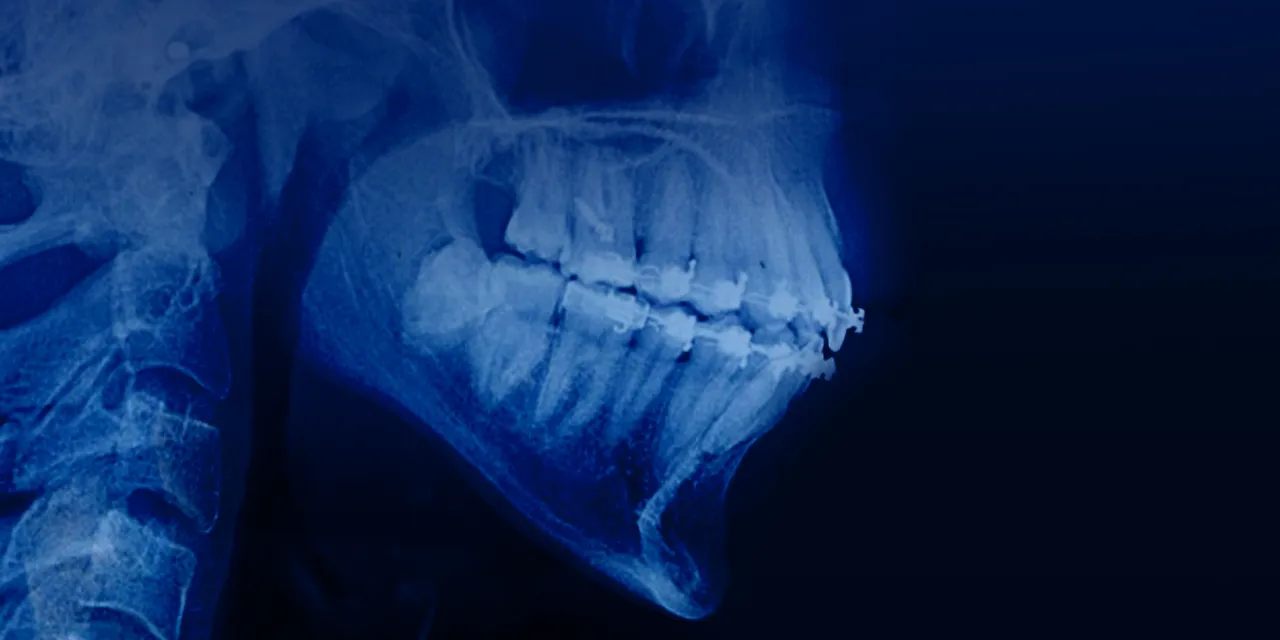

New online course for orthodontists on how to perform orthodontic treatment in patients with periodontal and alveolar bone pathology.

The OHI‑S Orthodontic Treatment in Patients with Periodontal and Alveolar Bone Pathology program is best for orthodontists, periodontists, restorative dentists, and oral surgeons who want structured, training in managing orthodontic cases complicated by reduced periodontal support or alveolar bone defects. It emphasizes evidence‑based, interdisciplinary protocols to achieve safe tooth movement, functional stability, and long‑term periodontal health.